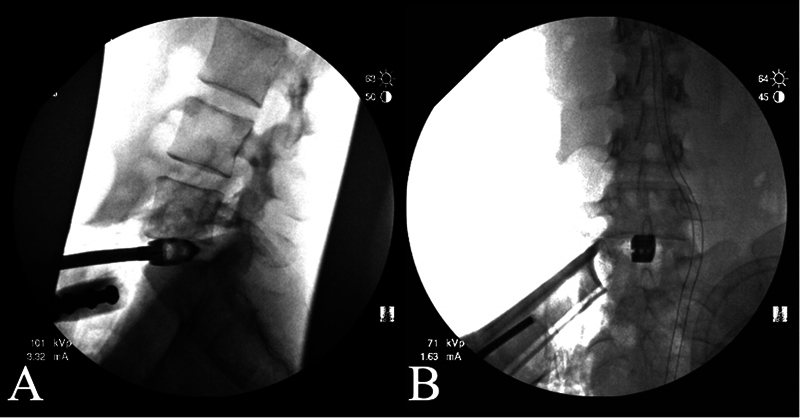

The aim of this study was to demonstrate that anteriorly placed transforaminal lumbar interbody fusion (TLIF) footprint bullet cage is a safe and effective bailout option if difficult left common iliac vein (LCIV) anatomy is unexpectedly encountered during the L5-S1 lateral anterior lumbar interbody fusion (L-ALIF). This retrospective case series includes four patients who received anteriorly placed TLIF cages at L5-S1 during L-ALIF surgery. Demographics, complications, and clinical/radiographic results were collected. The analysis included four female patients with a mean age of 59.0 years and mean body mass index (BMI) of 23.9. Three patients had degenerative conditions and one patient had a deformity. All the patients had an LCIV obstructing the center of the L5-S1 disk space, and titanium TLIF bullet cages were placed and secured with washers and screws. The L5-S1 segmental lordosis increased by 8.3 ± 6.1 degrees with a final mean lordosis of 23.5 ± 8.4 degrees; the L5-S1 intradiskal angle increased by 12.0 ± 7.0 degrees with a final mean disk angle of 18.8 ± 7.0 degrees; the posterior disk height increased by 4.4 ± 2.7 mm with a final mean disk height of 8.0 ± 2.1 mm. The mean numerical rating scale (NRS) for back pain improved by 5.3 ± 2.5 and the mean NRS leg pain improved by 7.7 ± 2.5 over a mean follow-up of 14 months (range: 6-20). There have been no perioperative complications or implant failure to date. If challenging vascular anatomy is encountered during L-ALIF exposure that prevents ALIF footprint cage placement, proceeding with smaller TLIF bullet cage placement anteriorly rather than abandoning the surgical approach is a safe and effective option.